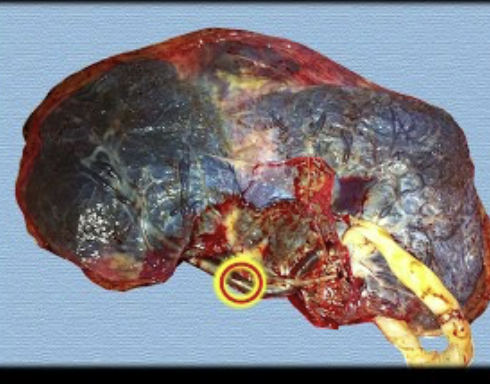

A 28-year-old in her first pregnancy has a spontaneous vaginal delivery at term, followed by post-partum haemorrhage, just after the placenta is delivered. The doctor managing the emergency asks the midwife to check for placental integrity.

Regarding placental anatomy, which one of the following statements is true?

Question 1 Answer

a.

It originates from the inner cell mass of the blastocyst

b.

Its thickness at the centre is ~ 4 cm

c.

A spiral artery usually supplies 3-4 cotyledons

d.

It contains 15-20 cotyledons

A